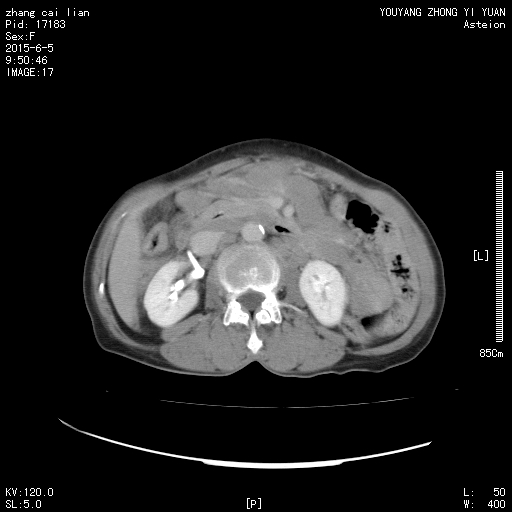

患者,女性,65岁。发现腹股沟包块1个多月。病人无发热,有消瘦。病人本来扫的是下腹部,后来发现有淋巴结肿大,又加了几层。

1、腹腔、盆腔、腹膜后及左侧腹股沟广泛淋巴结肿大,其中腹腔内部分病灶融合成团块状。

2、盆腔少量积液。

3、脾脏增大征象,实质密度正常。

4、右下腹不规则明显环状强化灶,其内低密度无强化,内壁不光整,边界与邻近肠组织结构欠清。

基于以上4点,考虑

1、原发性淋巴瘤。(但不好解释右下腹环状强化灶)。

2、如果右下腹病灶为原发灶的话,那么小肠淋巴瘤并广泛淋巴结转移,可一元论搞定。

所以个人比较倾向于第2个意见。